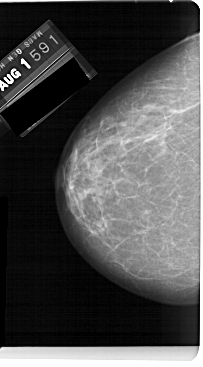

A_1563_1.LEFT_CC

LEFT_CC LINES 5491 PIXELS_PER_LINE 3031 BITS_PER_PIXEL 12 RESOLUTION 43.5 NON_OVERLAY